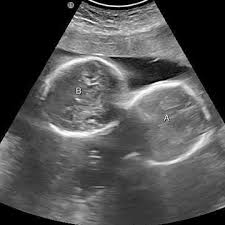

अल्ट्रासाउंड जांच में महिला के गर्भ में दो बच्चों की पुष्टि हुई थी

इंदौर। इंदौर के ESIC अस्पताल से प्रेगनेंसी का एक बेहद चौंकाने वाला मामला सामने आया है. यहां पर एक महिला ने तीन बच्चों को जन्म दिया. इससे भी ज्यादा हैरान कर देने वाली ये है कि जब डॉक्टर ने डिलीवरी से पहले अल्ट्रासाउंड किया था तब रिपोर्ट में दो बच्चे ही दिख रहे थे. लेकिन जब महिला ने तीन बच्चों को जन्म दिया तो डॉक्टर भी हैरान रह गए।

हॉस्पिटल के डॉक्टरों का मानना है कि ऐसे केस मेडिकल फील्ड के रेयर केसेस में से एक होते हैं. महिला ने 1 बेटा और 2 बेटियों को जन्म दिया है. अधिकारी ने बताया कि कर्मचारी राज्य बीमा निगम (ईएसआईसी) के चिकित्सा महाविद्यालय से जुड़े अस्पताल में 27 वर्षीय महिला ने दो लड़कियों और एक लड़के को रविवार (29 मार्च) को सामान्य तरीके से जन्म दिया. इस प्रसव के बाद जच्चा व तीनों नवजात शिशु स्वस्थ हैं।